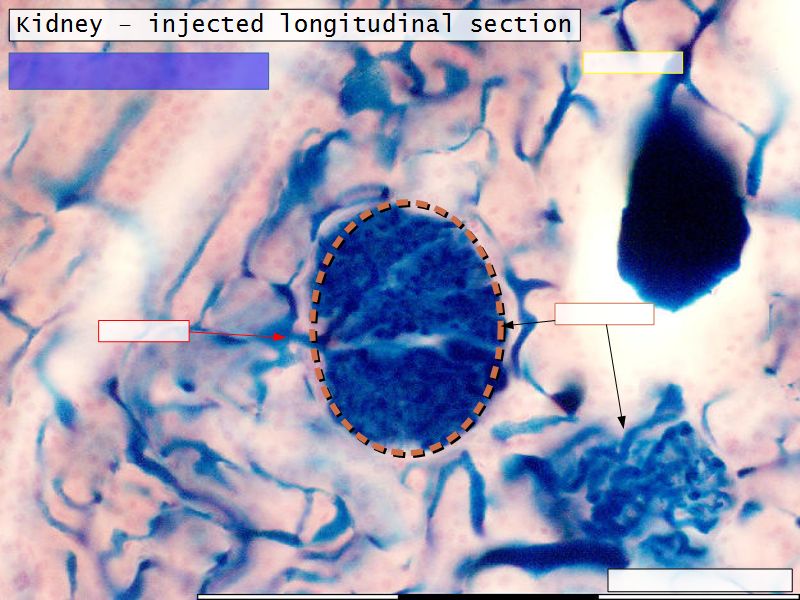

Renal corpuscle

- Tuft of capillaries

- grow into

- Blind end of nephron

- Several layers of epithelium

- Two sides

- Vascular pole

- Tubular pole

Blood flow

- Efferent arteriole

- Smooth muscle in media

- Capillaries

- Fenestrated

- Afferent arteriole

- Smooth muscle in media